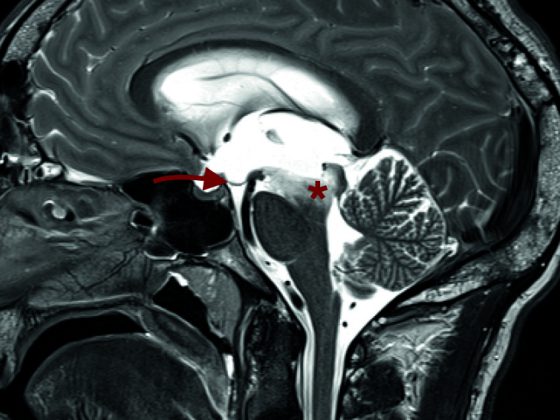

I pazienti naïve alla chemioterapia con plauramesotelioma avanzato e non resecabile hanno partecipato allo studio di fase Ib. Al momento della presentazione, sono stati valutati i dati di 38 pazienti. La Figura 1 mostra il regime terapeutico.